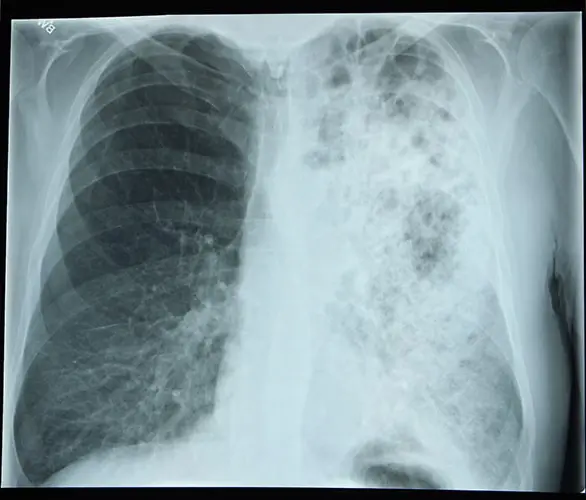

The image above is an X-ray showing lungs with Legionnaire's disease. Legionnaires' disease often looks similar to a chest X-ray to other types of pneumonia.

Legionnaires’ disease is very similar to other types of pneumonia (lung infection), with symptoms that include: